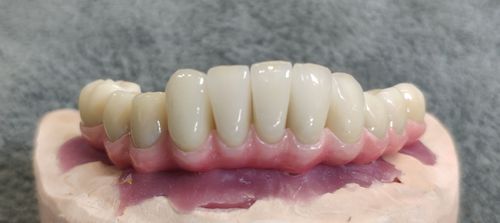

种植牙半口桥架与传统的义齿相比,美观度更高。它能够完美地融入口腔,与自然牙齿一样,形态与颜色也与周围牙齿相似,让人感觉非常自然。这种修复方式能够让缺失的牙齿得到良好的修复,让人的嘴巴焕发出新的笑容。

与其他修复方式相比,种植牙半口桥架的美观度更加突出。无论是在社交场合还是在日常生活中,它都能让人拥有自信的笑容,让人更加美丽自信。

种植牙半口桥架的材料非常安全,不存在对人体的副作用,也不会对周围的牙齿造成影响。它的修复效果非常好,能够帮助人们恢复美丽的笑容。